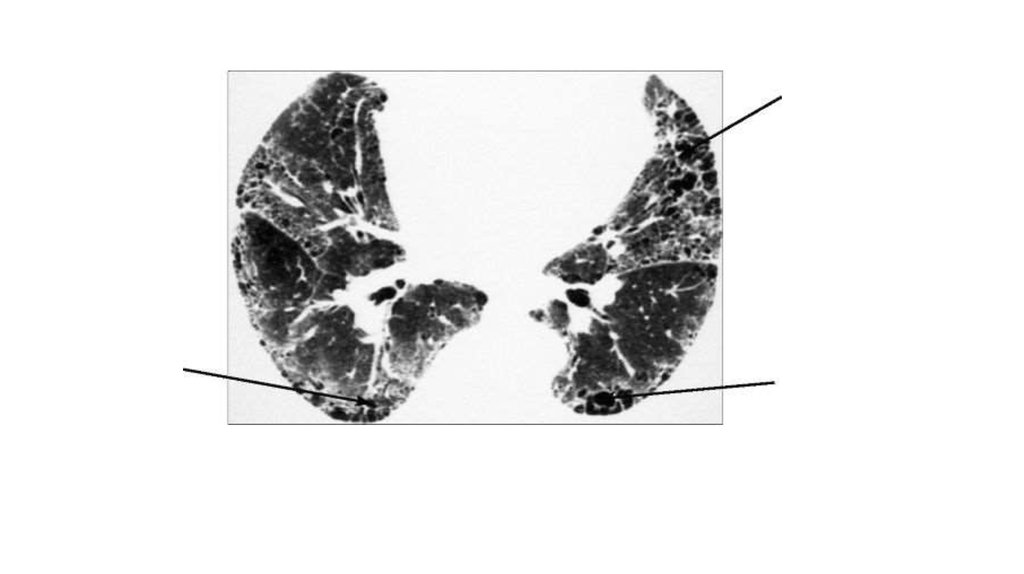

• КТ. «Сотовое легкое». В поздней стадии идиопатического

легочного фиброза образовались обширные области деструкции

нормальной паренхимы легких, представляющие собой зоны

крупноячеистого фиброза (стрелки)